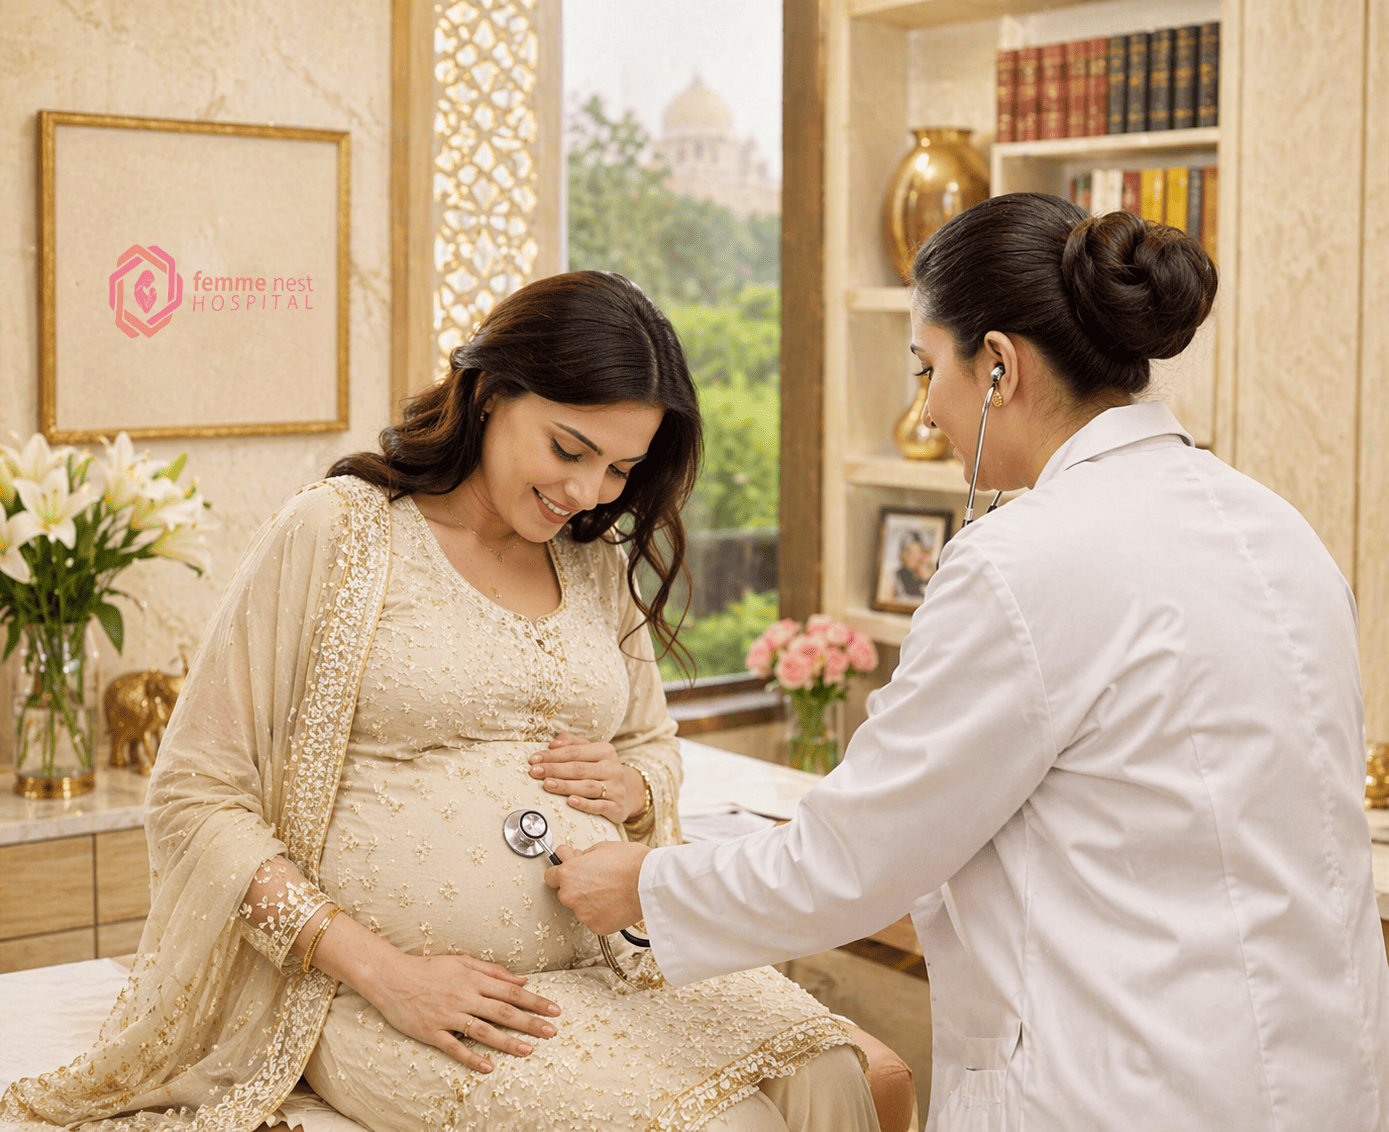

Boutique Hospital

for Women & Child Care

Where every journey to motherhood begins with world-class care.

Nurturing Women,

Welcoming Life

Compassionate maternity care for every stage of your journey.